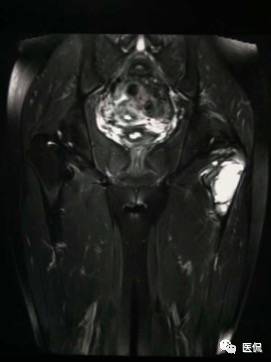

影像资料:

(3)MRI ABC的特征为鼓囊状的膨胀性破坏,呈单囊或由低信号的间隔分隔成大小不等的多囊。因血细胞和血浆的分离和沉淀,囊内可见液-液平面。在T2WI上,液面上层为高信号,下层为低信号;T1WI上则相反,上层为低信号,下层为偏高信号。液-液平面是ABC较特征的征象。增强检查低信号的纤维间隔呈环形强化。继发性动脉瘤样骨囊肿可在其原发病灶内有液-液平。

【诊断要点】发生于青少年长骨干骺端偏心膨胀的溶骨性病变,MRI检查病灶内见有液-液平征象时应首先考虑为动脉瘤样骨囊肿。